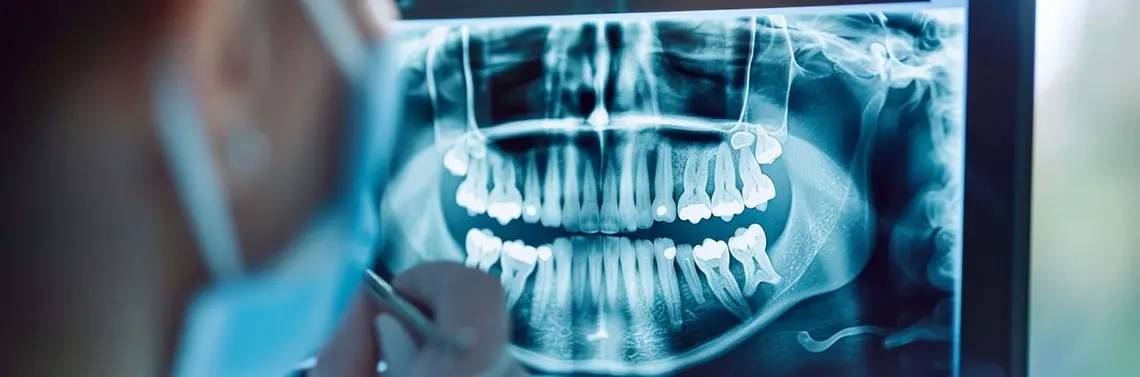

45-letni pacjent zgłosił się do poradni protetyki stomatologicznej w celu oceny oraz odbudowy zębów w żuchwie. Zlecono wykonanie badania TK żuchwy – badania OPG (zdj. 1A–J).